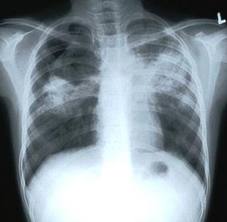

بمناسبة اليوم العالمي للدرن والذي يحل في 24 مارس من كل عام ( الموافق 1 / 5 / 1433 من هذا العام) أقدم هذه النشرة المختصرة للإخوة والأخوات الزملاء والزميلات راجيا أن تعم بها الفائدة والله الموفق . مرض الدرن ( السـل ) [align=center] ما هو الدرن؟ [/align]الدرن (السل) هو أحد الأمراض المعدية المزمنة التي قد يتعرض الإنسان أو الحيوان للإصابة بها , وينشأ نتيجة الإصابة بميكروب الدرن . [align=center] أنواع الإصابة بالدرن: [/align] 1– الدرن الرئوي . 2 – الدرن خارج الرئة: ويصيب الأعضاء خارج الرئة مثل:الغدد الليمفاوية – العظام – الجهاز العصبى – الحنجرة - القناة الهضمية – العين – الجلد . [align=center] ميكروب الدرن: [/align] هناك نوعان من ميكروب الدرن: 1- ميكروب الدرن البشري (أكثر من 99% من الحالات) . 2- ميكروب الدرن البقري (أقل من 1% من الحالات) . [align=center]طرق العـدوى:[/align] 1 – يمثل الجهاز التنفسى المصدر الرئيسى للعدوى بالدرن وينتقل الميكروب إلى الجهاز التنفسى عن طريق استنشاق قطيرات رذاذ المريض المحملة بالميكروب والناشئة عن سعال المريض بالدرن أو عطاسه , وكذلك عن طريق تدخين الشيشة عندما يكون أحد المدخنين مصاباً بالدرن . 2 – قد ينتقل الميكروب إلى اللوزتين أو القناة الهضمية عن طريق شرب لبن ملوث مصدره أبقار مصابة بالدرن أو تناول منتجات ألبان ملوثة بالميكروب . [align=center]عوامل زيادة احتمالات الإصابة بالمرض:[/align] 1– مخالطة المرضى المصابين بالدرن الرئوى النشط . 2– الازدحام وتلوث البيئة وسوء التهوية . 3– الفقر وانخفاض مستوى المعيشة . 4– الجهل وعدم إتباع التعليمات الطبية للوقاية من المرض . 5 – بعض الأمراض تزيد من احتمالات الإصابة بالدرن مثل: البول السكرى ، الفشل الكلوى ، مرض نقص المناعة المكتسبة (الأيدز) ، العلاج لفترات طويلة بمركبات الكورتيزون ، بعض الأمراض الخبيثة مثل سرطان الدم . ما هو الفرق بين الإصابة بالميكروب ومرض الدرن؟ • تختلف الإصابة بميكروب الدرن عن حدوث مرض الدرن ، لأن معظم الذين يصابون بميكروب الدرن لا تظهر عليهم أعراض المرض ولا تتحول الإصابة لديهم إلى مرض . ويعتبر المرض موجودا إذا اشتكى المريض من أعراض المرض وأمكن اكتشافه بوسائل التشخيص مثل فحص الأشعة أو الفحص المعملى للبصاق أو غيره من العينات . ما هى أعراض المرض؟ • أعراض عامة : وهى ارتفاع فى درجة الحرارة ، عرق ليلى ، فقدان الشهية ونقص الوزن . • أعراض رئوية وهى سعال ، بصاق مدمى (بصاق معرق بالدم أو دماً صريحاً) ، ألم بالصدر نتيجة التهاب الغشاء البلورى . • قد يشكو المريض من ضيق التنفس نتيجة الانسكاب البلورى الدرنى ، الالتهاب الرئوى الدرنى ، الكهوف الدرنية ، الالتهاب الشعبى الدرنى . كيف يمكن تشخيص الدرن الرئوى؟ • 1 – الفحص الإكلينكى . • 2 – الفحص بالأشعة . • 3 – الفحص المعملى لميكروب الدرن فى البصاق وعينات أخرى . • 4 – فحص الدم . • 5 – اختبار التيوبركولين ( اختبار عن طريق الجلد ). [align=center]كيف يمكن علاج الدرن؟[/align] تستخدم عدة أدوية معا لعلاج الدرن (قد يصل عددها إلى خمسة أو أكثر) ولمدد طويلة (من ستة أشهر إلى سنتين أو أكثر ) ولابد من الالتزام بجرعات الأدوية والمدة التي يحددها الطبيب كي لا تنتكس الحالة أو تكتسب الميكروبات مناعة ضد الأدوية , وأحيانا تستدعي بعض الحالات التدخل الجراحي إلى جانب الأدوية , ولقد قامت الحكومة السعودية مشكورة بتوفير علاج الدرن مجانا للمواطنين والمقيمين . التطعيم ضد الدرن: يستخدم لقاح الدرن (بى.سى.جى) فى تطعيم حديثى الولادة عادة عند عمر شهر كذلك يستخدم – فى الأشخاص ذوي اختبار سلبى للتيوبركولين إذا كانوا أكثر تعرضاً للإصابة بالميكروب نتيجة مخالطة المرضى بالدرن . ( مع أطيب التمنيات لكم ولسائر المسلمين بدوام الصحة والعافية ) التعديل الأخير تم بواسطة أحمد صلاح الحفني ; 2014-03-30 الساعة 10:51 PM. |